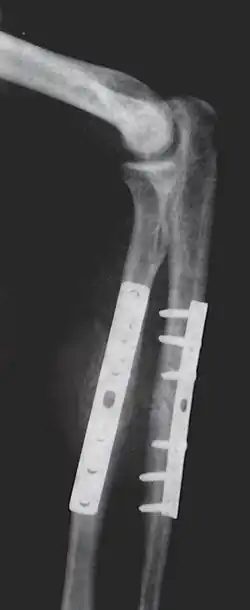

Orthopedic surgery or orthopedics (alternative spelling orthopaedics) is the branch of surgery concerned with conditions involving the musculoskeletal system.[1] Orthopedic surgeons use both surgical and nonsurgical means to treat musculoskeletal trauma, spine diseases, sports injuries, degenerative diseases, infections, tumors and congenital disorders.

- Repair fracture of radius/ulna

Arthroplasty is an orthopedic surgery where the articular surface of a musculoskeletal joint is replaced, remodeled, or realigned by osteotomy or some other procedure.[25] It is an elective procedure that is done to relieve pain and restore function to the joint after damage by arthritis (rheumasurgery) or some other type of trauma.[25] As well as the standard total knee replacement surgery, the unicompartmental knee replacement, in which only one weight-bearing surface of an arthritic knee is replaced, may be performed,[25] but it bears a significant risk of revision surgery.[26] Joint replacements are used for other joints, most commonly the hip[27] or shoulder.[28]